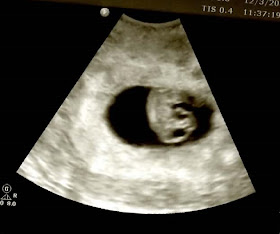

I was 7 weeks and 3 days and we got to see Baby LB and his/her heartbeat. It was an awesome day. We got a great picture of him/her.....

It was really amazing to se him/her hanging around in there. We were over the moon. I was sad to hear at that appt. that I would no longer need to see my RE. Since baby was measuring right on target and had a nice strong HB we have no need to go back insert depressed face here> there were lots of hugs and such. It's a scary feeling to "graduate" from your RE.

I've been doing a lot of praying. A LOT of praying. This whole situation is still very surreal to me. I really can't believe I made it this far. I sometimes just sit and stare at the u/s picture in complete and utter disbelief that THAT is OUR baby. When I hugged my RE for the last time on Thursday and thanked her I don't think anything words I could have said would have sufficed for how grateful I am to her. How do you thank the person who helped give you a child?! How do you ever express that in words? I've been waiting for a good day to sit and write her a letter. I don't want to just send a regular old thank you card and gift.